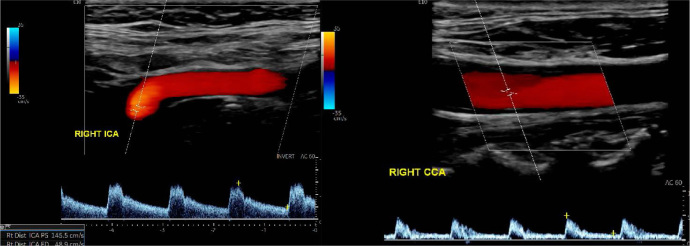

Since the first clinical use of ultrasound in the 1940s, significant advancements have been made in its applications. Color Doppler imaging and power Doppler imaging are considered the first and second generations of flow ultrasound assessment tools, respectively. Subsequently, the introduction of contrastenhanced ultrasound has significantly improved the assessment of arterial and venous vascular patterns in lesions and vessels. 'Blood flow brightness-mode imaging' or 'B-flow', a non-Doppler ultrasound flow assessment mode introduced more recently, provides even more information for ultrasound users in flow assessment. Microvascular imaging, introduced about a decade ago, is the third generation of Doppler non-contrast ultrasound flow modes, and is growing in popularity. Using a special wall filter, microvascular imaging overcomes the limitations of color Doppler imaging and power Doppler imaging in the detection of slow flowing signals. Advanced dynamic flow is a third-generation non-contrast Doppler flow technology that has so far gained popularity in obstetric ultrasound, commonly used to evaluate fetal umbilical vessels and heart chambers. This review article presents some recent updates on the various non-contrast ultrasound flow modalities available in clinical practice. It focuses on the design principles of individual flow modalities, discussing their strengths, limitations, and clinical applications, along with a review of the relevant literature.